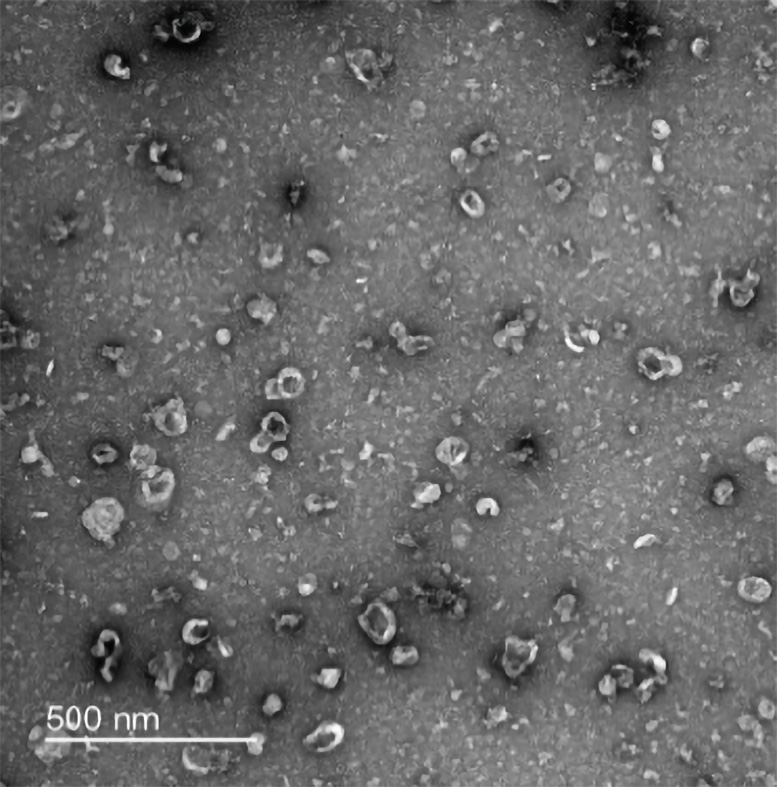

נעשה שימוש במיקרוסקופיה של שידור אלקטרוני של כתם שלילי כדי לאשר את הבידוד של שלפוחיות חוץ-תאיות קטנות בנוירונים של עכברים (המוצג לעיל), כמו גם באסטרוציטים ומיקרוגליות של עכברים. קרדיט: מעבדת צ'ון